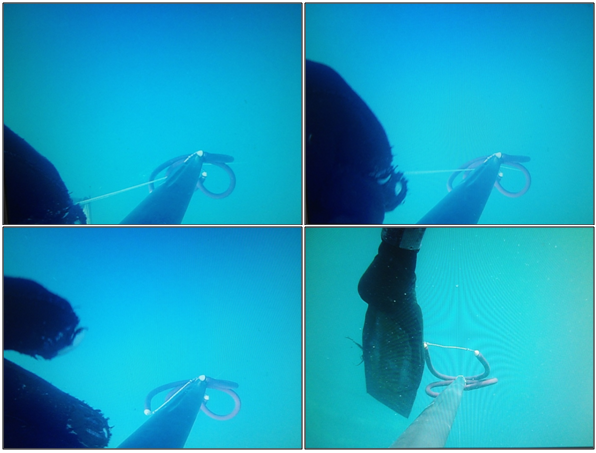

Chemical findings: 5 bodies from the Sw have been investigated. In 4 cases was significantly positive for Sr and Si. The only negative for Sr and Si was a 37 years old subaqueous swimmer and the death was recorded by a camera (Figure 9): histologically, the lungs tested were negative for plankton; disseminated myocardiosclerosis was microscopically identified (sudden death). In Fw, Si was positive in 4/5 cases.5

Figure 9 Sudden cardiac death. A 37 years old subacquoeous swimmer had plunged in apnea to 40 meters deep. Still images from underwater video (the camera was fixed on the speargun and was recovered on the sea bed): frames A and B (at second 4th and 5th), the speargun is held by the hand of the swimmer; frame C (at second 7th), the hand leaves the rope; frame D (at second 18th), the speargun moves away from the body and records a right foot flipper. The timing of frames shows the sudden stop of motor functions.